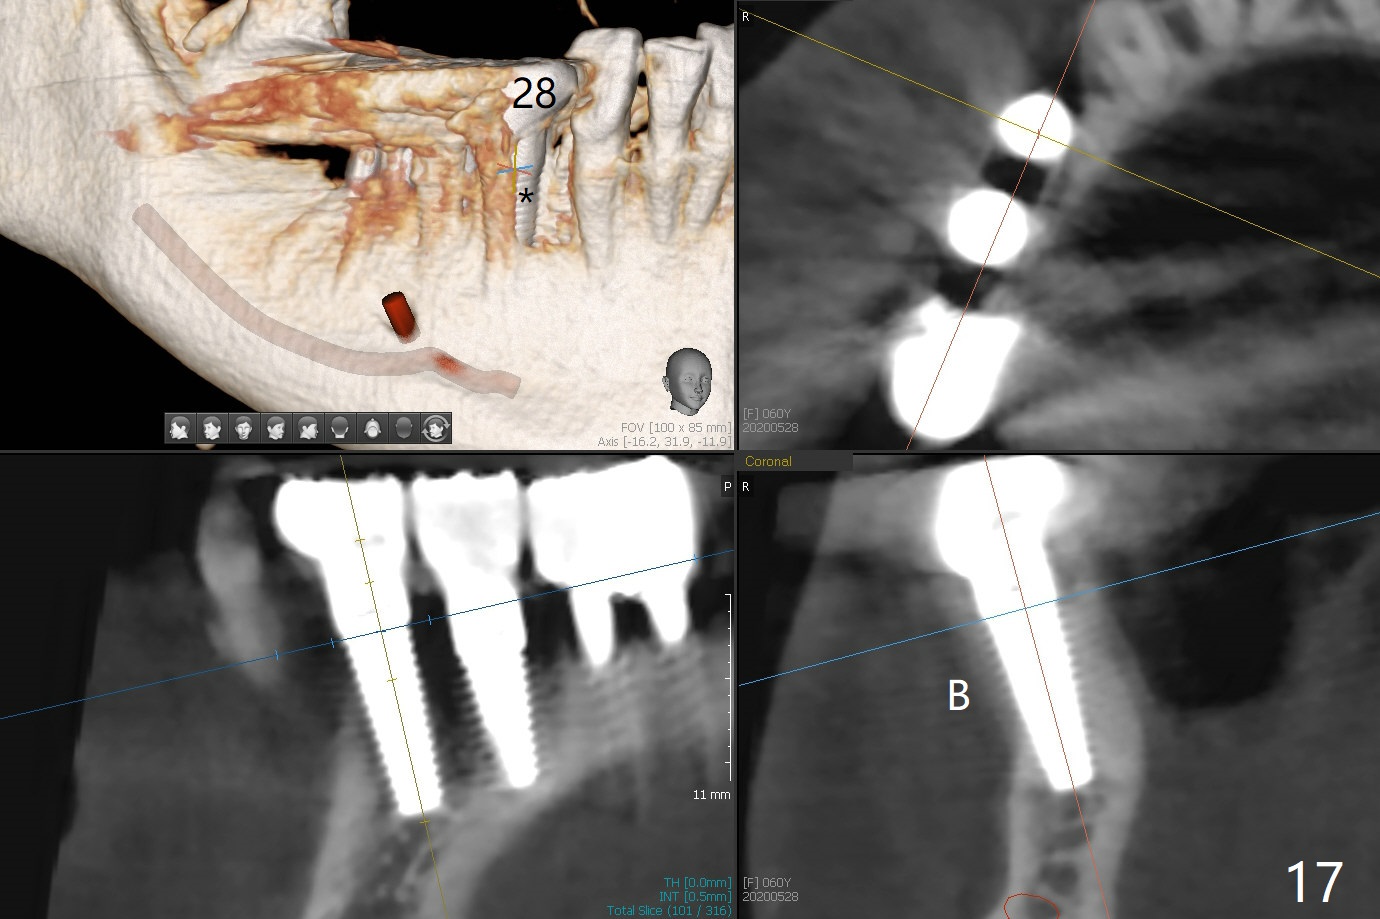

The edentulous ridge at #30 is narrow (Fig.1). After ridge reduction, osteotomy is initiated with 1.2 mm drill for 10 mm; the mesial osteotomy is to be changed (Fig.2 red line). Using a 1.2 mm drill placed in the distal osteotomy (Fig.3 D), the mesial osteotomy changes in trajectory with subsequent placement of a 2.5x10(4) mm 1-piece implant. Since the mesial implant is high in occlusion, the cuff of the distal implant is changed to be 2 mm (Fig.4 (shorter black line)). Panoramic X-ray is taken to show no violation of the Inferior Alveolar Canal (Fig.5 red dashed line). These two 1-piece implants are slightly lingually placed (Fig.6). The crestal bone around the implants resorbs without thread exposure 5 months postop (Fig.7). Impression is taken for a splinted crown (Fig.8-12). There is no metal show around the 2.5 mm 1-piece implants 6 months postop (advantage) vs. that at #28 and 29 (Fig.13). Bitewing is taken post cementation to determine whether residual cement is present (Fig.14). There is periodic swelling and pain in the lower right quadrant 2 years post cementation (Fig.15). In fact periimplantitis appears to have developed at #28 (Fig.16) with loss of the buccal bone (Fig.17,18). The buccal bone loss is less at #29 (Fig.19) and #20 (Fig.23) and no at #30 mesial and distal implants (Fig.20,21). A much smaller implant will be placed lingually at #28 immediate (Fig.24,25).